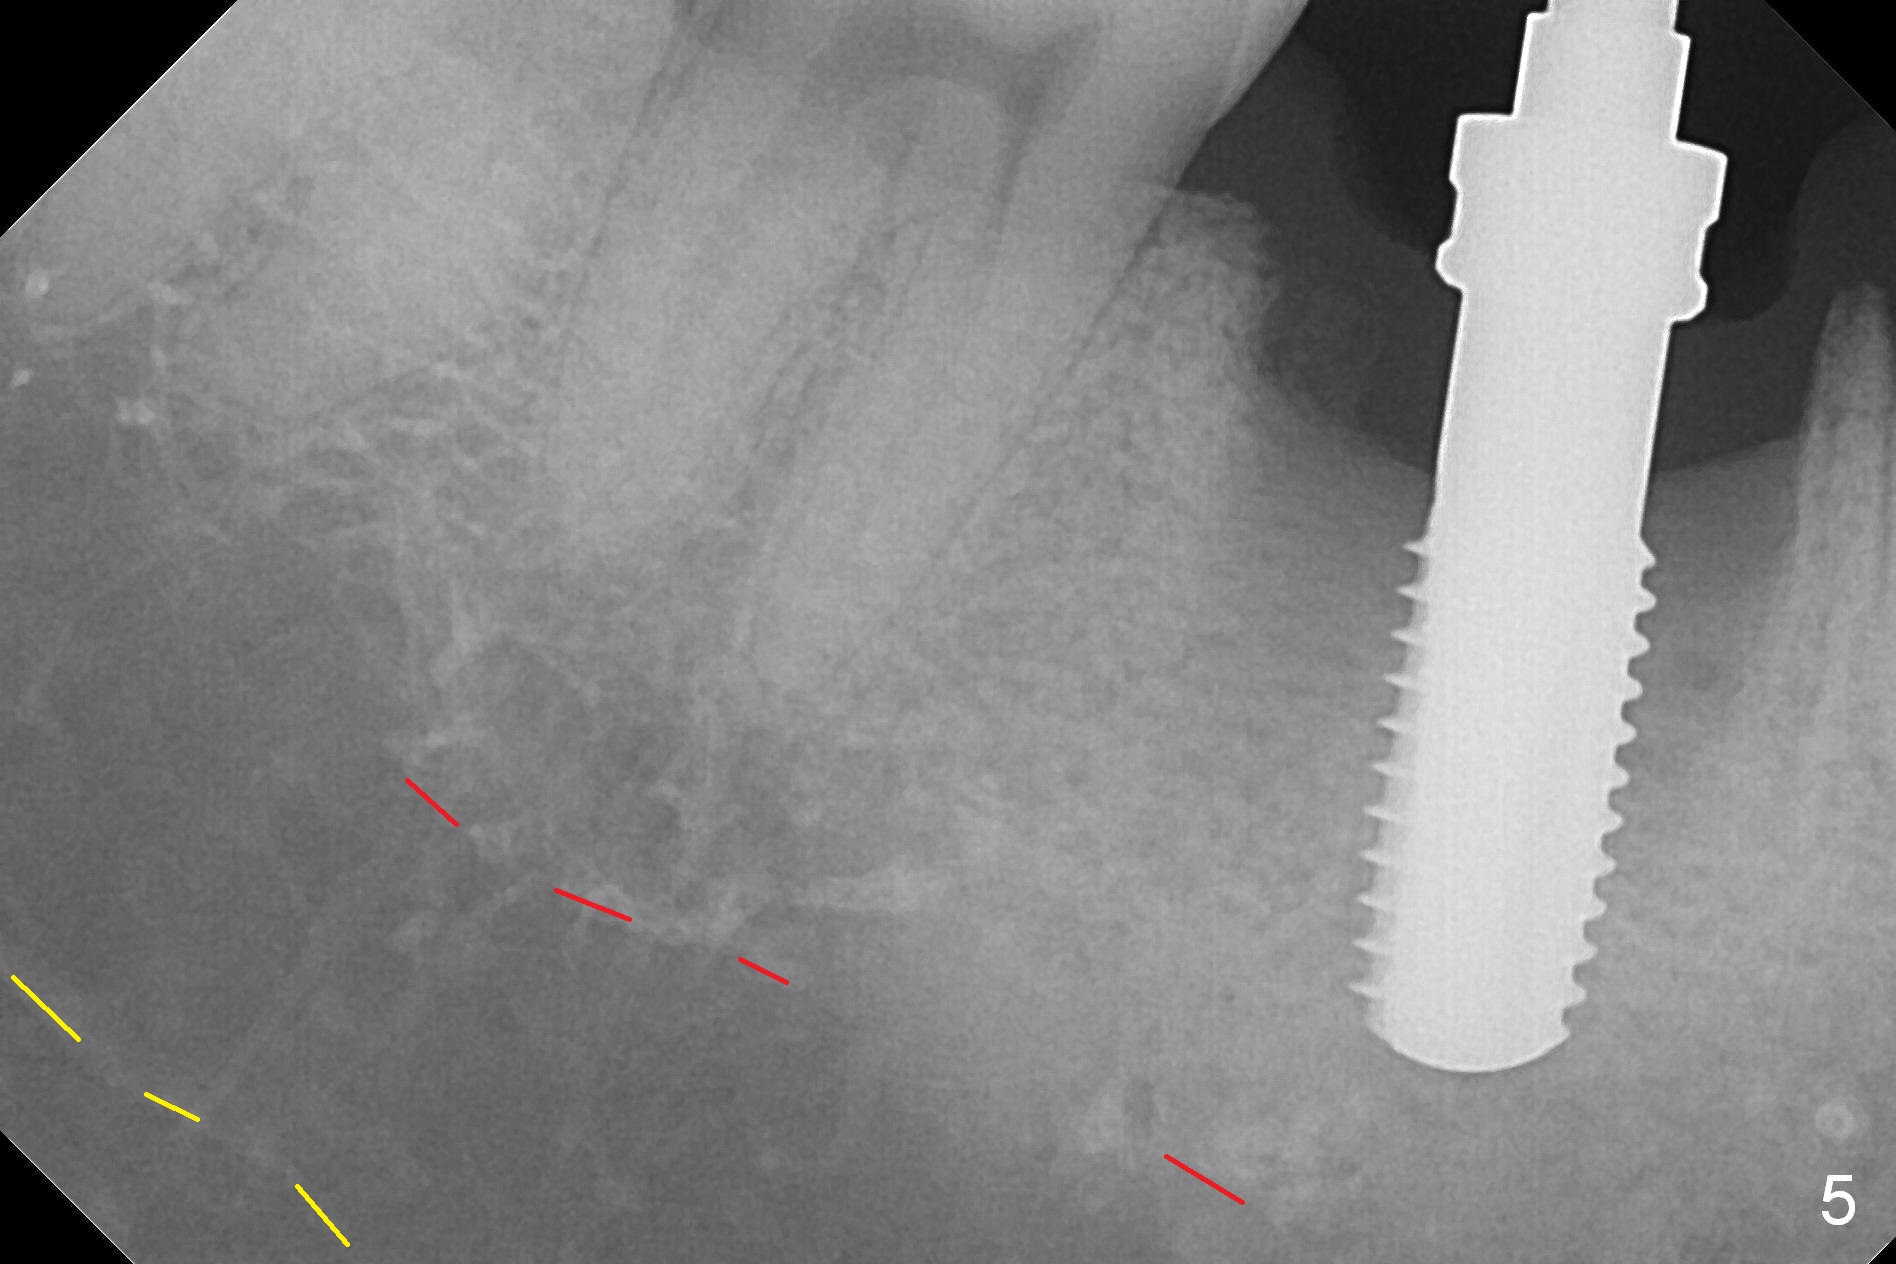

After extraction of the tooth #30 with Class V furcation involvement (Fig.1 (>),2 (L: lingual)), initial osteotomy depth is 8 mm with infiltration anesthesia, but a parallel pin is able to be inserted for 16 mm without pain (Fig.3). There is oozing from the osteotomy. Osteotomy increases in diameter with depth at 8 mm (Fig.4 (3.8 mm drill),5 (5.3 mm tap)). As the Inferior Alveolar Canal (IAC) is indistinct with increased pain during osteotomy, a 5.9x6 mm implant is placed with >50 Ncm following Septocaine infiltration (Fig.6). When bone graft (Fig.7 *) and 7.8x5.5(6) mm abutment (Fig.7,8) are placed, panoramic X-ray is taken (Fig.9). There appears to be a thick layer of spongy bone in the posterior mandible between the red and yellow dashed lines (Fig.5,9). Panoramic X-ray and/or CBCT should be taken if preop PA does not reveal IAC. This patient seems to be a bruxer. There are mandibular tori. Bone loss (furcation involvement) is not proportional to his oral hygiene status. Functional loading (progressive) should be delayed due to bruxism and the short implant.